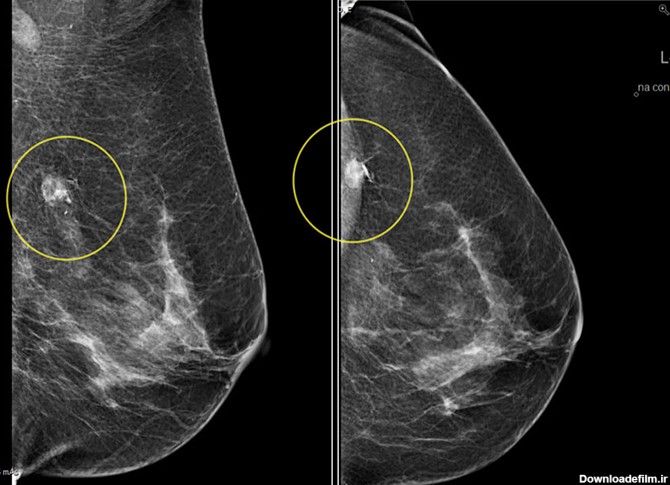

ماموگرافی هالوژیک یا ماموگرافی معمولی به این صورت می باشد که عکس گرفته شده از بیمار روی فیلم رادیولوژی ثبت می شود و مشابه همان عکس طی یک فرآیند به چاپ می رسد

ماموگرافی سه بعدی هالوژیک؛ماموگرافی سه بعدی در مرکز جردن به پزشکان کمک می کند تا از نظر سرطان سینه به طور کامل غربالگری کنند